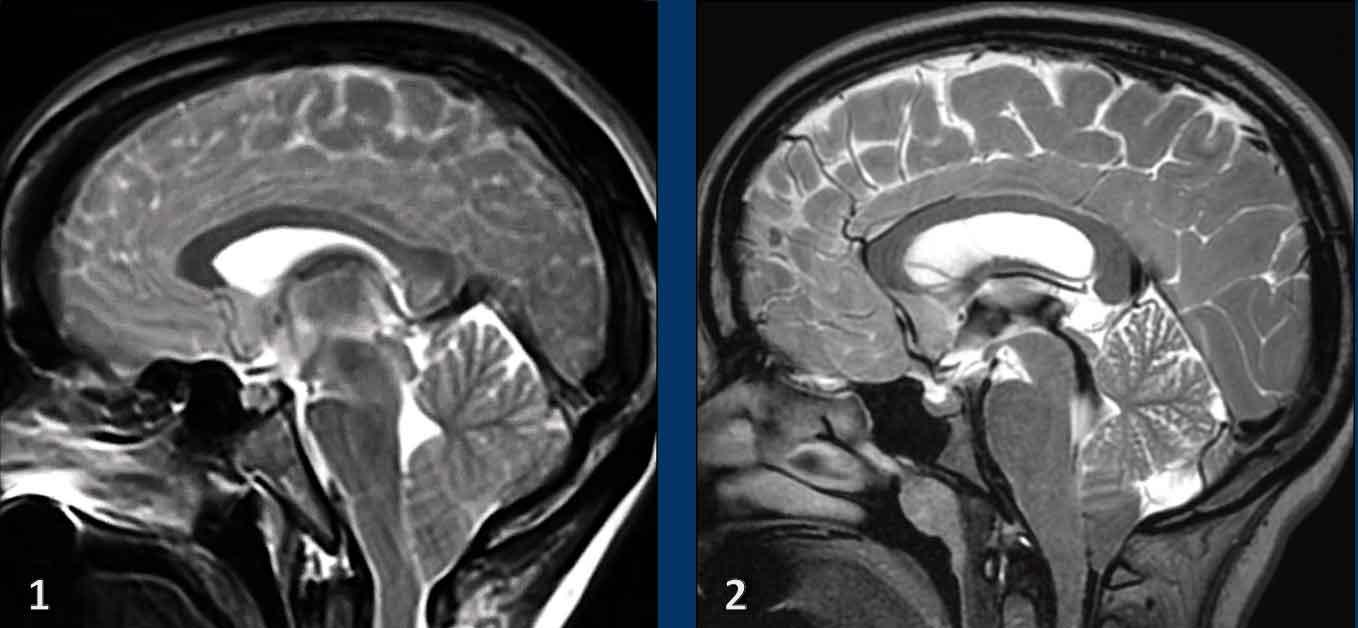

Trung não bị võng xuống

Trong các trường hợp SIH nặng hơn, não bị dịch chuyển xuống dưới, dẫn đến thân não bị chèn ép vào nền sọ.

Dấu hiệu này được gọi là “thân não bị trượt xuống” hoặc “trung não bị võng xuống” và được coi là đặc hiệu cho hạ áp nội sọ.

Trong điều kiện bình thường, các thể vú nằm phía trên lưng yên và khoảng cách đến cầu não ít nhất là 5,5 mm.

Khi trung não bị võng xuống, khoảng cách đến cầu não nhỏ hơn 5,5 mm.

Trên các lát cắt axial, sự dịch chuyển xuống dưới của não dẫn đến chèn ép trung não.

Hình ảnh

- Hình ảnh võng xuống với trung não bị chèn ép từ hai phía (vòng tròn).

- Trung não bình thường để so sánh.

Ở bệnh nhân SIH này, tất cả các tĩnh mạch đều giãn và bờ của xoang tĩnh mạch ngang có dạng lồi.

Lưu ý thêm hình ảnh màng cứng dày và ngấm thuốc.